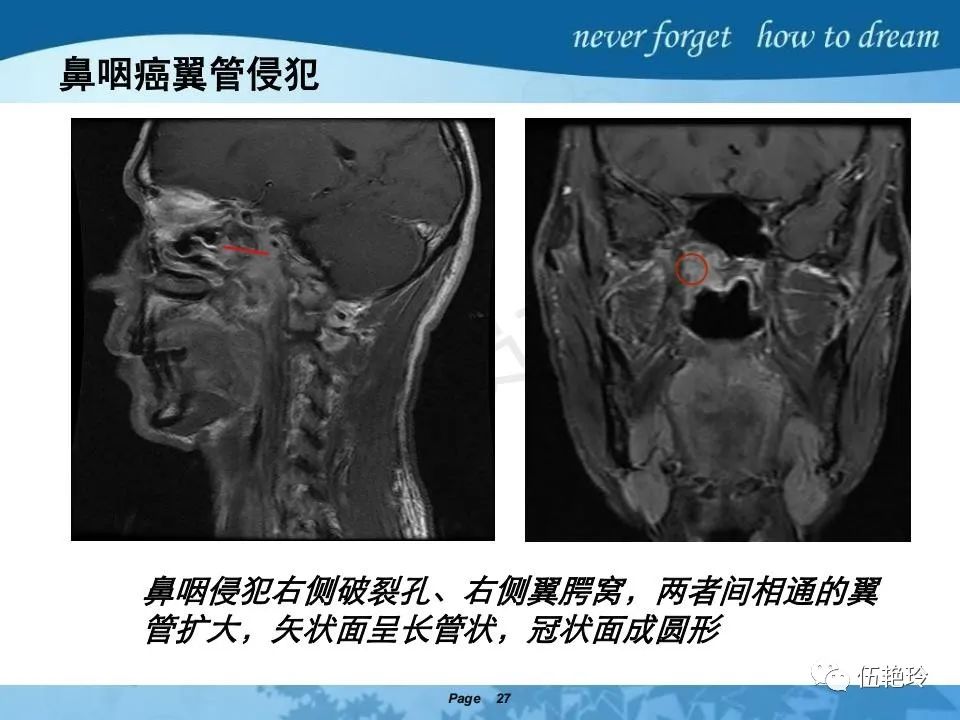

翼腭窝的解剖结构与鼻咽癌侵犯

2.31 向上颅内:①鼻咽顶壁→破裂孔(岩尖、斜坡)→蝶窦、海绵窦;②鼻咽顶壁→蝶骨基底部→蝶窦、海绵窦;③鼻咽侧壁→茎突前间隙→蝶骨大翼(卵圆孔)→海绵窦;④鼻咽侧壁→茎突前间隙→翼腭窝→ 颞下窝;⑤鼻咽前壁→鼻腔→翼突、翼腭窝→眶下裂→眶尖→海绵窦;⑥鼻咽前壁→鼻腔→上颌窦、筛窦;